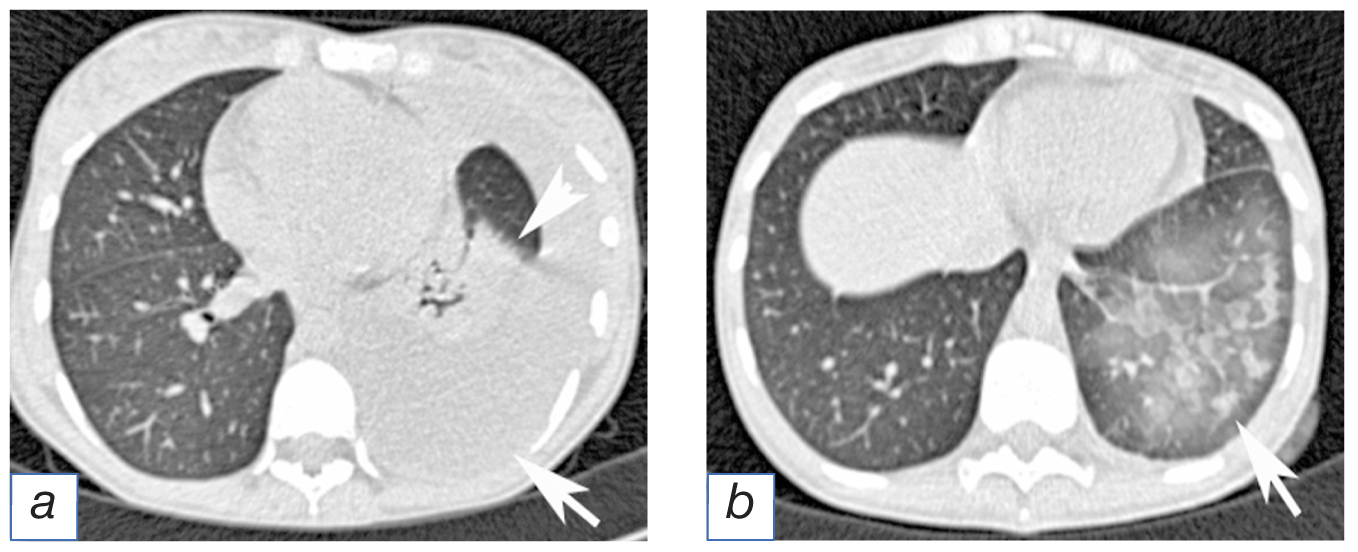

Laboratory and instrumental diagnostics. Upon performing the X-ray and computed tomography of the chest, pleural effusion was found, occupying the lower, the middle and partially upper segments of the left lung, along with the atelectasis of the lower lobe of the left lung (Fig. 1,2,а).

Therapy. 12G draining tube was installed along the left anterior axillary line in the fourth intercostal space. One hour after the installation of the draining tube and after removing ~1.6l of serous-hemorrhagic fluid into the air-locked hermetically sealed draining container, the patient started experiencing coughing with developing an acute shortness of breath and tachypnea with desaturation (SpO2) down to 83% (when inhaling oxygen, 5l/minute, via the simple breathing mask), accompanied by hypotension and tachycardia. Upon the computed tomography of the chest, the findings included a decreased transparency of the left lung (ground glass-type) with multiple intralobular foci of “consolidation” (see Fig. 2,б).

Fig. 2. Female patient К., 38 years of age. Computed tomography image of the thoracic cavity: а — effusion in the pleural cavity (arrow), collapsed lower lobe of the left lung (point of arrow); b — one hour after draining the pleural cavity: decrease transparence of the pulmonary tissue (ground glass-type), foci of consolidation within the basal segments left lung, caused by the reexpansion edema (arrow).

Diagnosis. Taking into consideration the anamnestic data and the clinical signs, the definitive diagnosis set was the following: “Reexpansion edema of the left lung, secondary in terms of hydrothorax of the left lung and in terms of the atelectasis in the lower lobe of the left lung”.